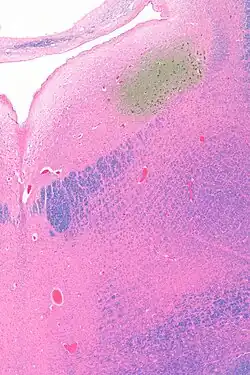

Anatomy

The locus coeruleus (LC) is located in the posterior area of the rostral pons in the lateral floor of the fourth ventricle. It is composed of mostly medium-size neurons. Melanin granules inside the neurons contribute to its blue colour. Thus, it is also known as the blue nucleus, or the nucleus pigmentosus pontis (heavily pigmented pontine nucleus).[5] The neuromelanin is formed by the polymerization of norepinephrine and is analogous to the black dopamine-based neuromelanin in the substantia nigra.